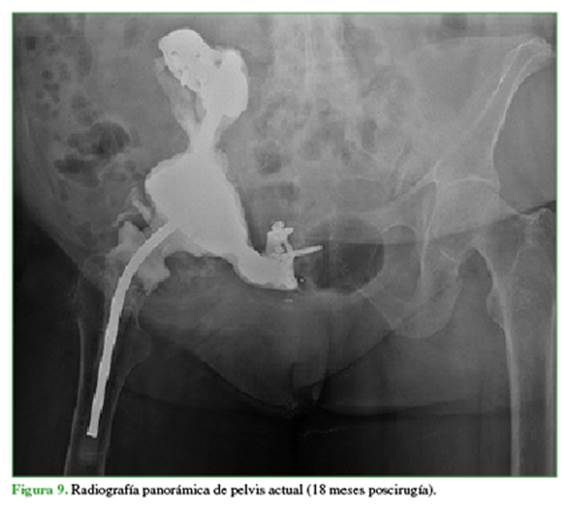

A los 18 meses, los parámetros de laboratorio eran normales, tanto inflamatorios (proteína C reactiva 0,3 mg/dl, eritrosedimentación 15 mm/h, glóbulos blancos 5600/mm3) como del metabolismo fosfocálcico (calcio 9,3 mg/dl, fósforo 3 mg/dl), no había signos clínicos de infección activa. Luego de discutir en un ateneo multidisciplinario, se propuso a la paciente la cirugía de reconstrucción definitiva de la hemipelvis derecha, a la cual se negó rotundamente, porque no tenía dolor y caminaba sin dificultades con un andador. Según el Servicio de Endocrinología, el plan será continuar el tratamiento con burosumab por tiempo indeterminado y realizar controles bimensuales de calcio y fósforo. Actualmente, en la radiografía, se puede constatar la correcta posición del espaciador, sin signos de aflojamiento ni de enfermedad activa (Figura 9).